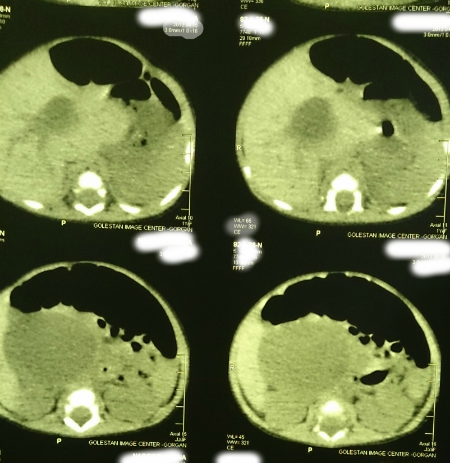

A 22-day-old female infant was admitted due to prolonged jaundice. She was icteric from the fourth day of life along with acholic stools and abdominal distension. Direct hyperbilirubinemia was detected in blood tests. Her total bilirubin and direct bilirubin were 19mg/dl and 10.3mg/dl respectively. Clotting profile was normal. Liver function tests (LFTs) were AST (84IU/L), ALT (81IU/L), and Alkaline phosphate (2024 IU/L). The abdominal sonography showed a choledochal cyst (56x43x46mm) with few echogenic areas in it. Wall thickness and echogenicity of gallbladder as well as intra hepatic ducts were normal. Abdominal CT scan confirmed the existence of choledochal cyst (Fig. 1). The patient was operated after optimization. Operative findings included an extra hepatic choledochal cyst (type I) which was ending blind on either sides. Porta-hepatis showed type III biliary atresia. The choledochal cyst and gallbladder had no bile but mucinous secretions which were aspirated. The gallbladder and choledochal cyst were resected; the porta-hepatis dissected and Roux-en-y porto-enterostomy was performed. The wedge biopsies from porta-hepatis showed biliary atresia as donated by diffused feathery degeneration, cholestasis, pseudoacinar transformation, focal giant cell, bile duct proliferation, and fibrotic tissue. The histopathology of choledochal cyst showed a biliary epithelial lining and that of gallbladder showed congestion and near total obliteration. Postoperatively, the jaundice improved and the patient passed pigmented stool. Patient was allowed orally and discharged on short course of prednisolone, fat soluble vitamins and prophylactic antibiotic. At present, the infant is 10- months old and thriving well. The last total bilirubin is less than 1.5mg/dl.

| Figure 1: Cyst at porta-hepatis. | |